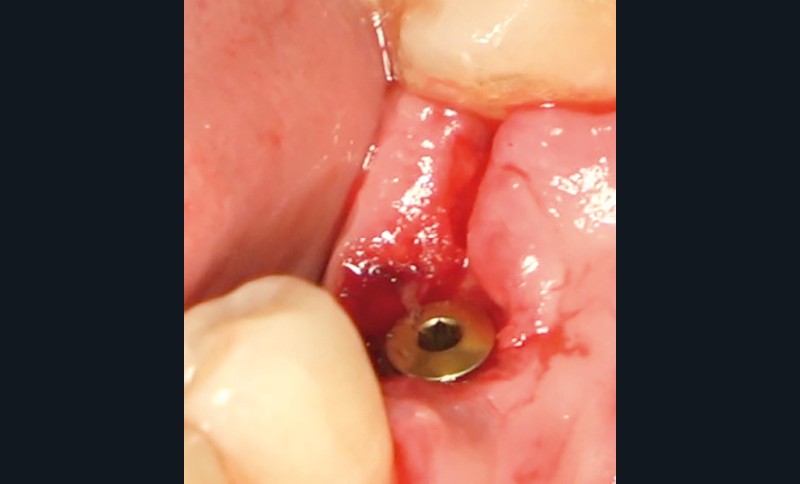

- Avulsion de la 36 et régénération osseuse guidée (ROG) réalisée en 2017 suite à une fracture de la dent et une infection

- Un implant posé en 2018 après la fin du traitement orthodontique

- Péri-implantite diagnostiquée en 2021